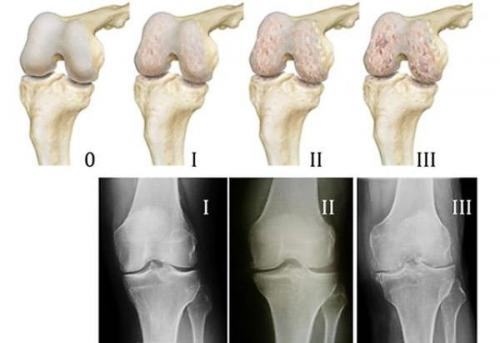

Медикаментозное лечение артроза коленного сустава эффективно лишь на I или II стадии заболевания, когда в дегенеративный процесс еще не вовлечены кости. Адекватно подобранные лекарственные препараты снимают неприятные симптомы, существенно замедляют развитие патологии. Со временем остеоартроз все же прогрессирует, а спустя годы приводит к безвозвратной потере функций коленного сустава.

Артроз III и IV степени практически не поддается консервативной терапии. Некоторые лекарственные препараты помогают временно облегчить боль, улучшить самочувствие больного, но никак не восстановить разрушенные кости и хрящи. На поздних стадиях артроза добиться успеха в лечении можно лишь с помощью операции — эндопротезирования коленного сустава.

Коксартроз (артроз тазобедренного сустава) 3 степени – стадия заболевания, когда происходят выраженные, необратимые изменения:

- Почти исчезает суставная щель.

- Хрящевая поверхность разрушена.

- Вертлужная впадина и головка тазобедренной кости становятся плоскими, увеличиваются в размерах из-за костных разрастаний по краям.

- Сустав сильно деформирован.

На первой и второй стадиях лечение коксартроза тазобедренного сустава будет наиболее эффективным. Нежели лечебные меры при запущенном заболевании. Так как разрушение сустава на раннем этапе возможно замедлить. А значит сохранить подвижность бедра. Сначала в независимости от степени деформации сустава доктор проводит классическое лечение.